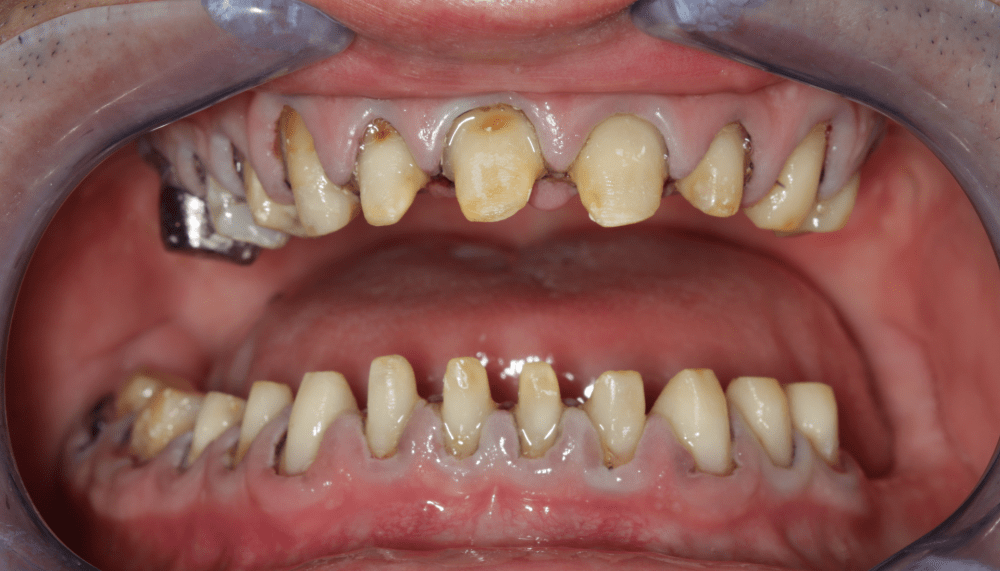

Klinikai és radiológiai vizsgálatok alapján megállapítottam, hogy a túlterhelés (parafunkciók) jelei látszódnak a fogain is: abfrakciók – nyaki kopások és attríciók –, rágófelszíni kopások is kifejezettek voltak. Harapása igen bizonytalan tartományban mozgott, nem volt egy stabil helyzet, amelybe határozottan össze tudott volna zárni (csak kereste a megfelelő pozíciót.) TMI-vizsgálat során reciprok crepitációt (kattanás nyitáskor-záráskor is), myofascialis eltéréseket (hypertrófiás musculus masseter – túlterhelt rágóizom) és beszűkült mozgáspályákat találtam. Emellett sajnos a nem megfelelő szájhigiénés szokások miatt a fognyakak „sérült” részein szuvasodások is megjelentek, illetve a bal alsó hatos és a jobb felső hetes fog már oly mértékben destruálódott, hogy el kellett távolítani őket.

A nagy kiterjedésű szuvasodások ellátására, továbbá a harapási forma és ezzel együtt az ízületi panaszok megszüntetésére full kontúr cirkón pótlást terveztem, melyet individuálisan a rendelőnk ARCUSdigma készülékének segítségével készítettem el.

Első lépésként előkészítettem a fogakat a pótláshoz (szuvas léziók eltávolítása, csonkkiegészítések kompozit tömőanyaggal, csonkpreparálás), és levettem a szükséges lenyomatokat.

Majd ezt követően arcívvel meghatároztam a felső állcsont koponyához való elhelyezkedését, intraorális rajzolóeszközzel a felső és az alsó állcsont egymáshoz való viszonyát, majd az Arcus Digma készülékkel az individuális mozgáspályákat. Ez mind szükséges ahhoz, hogy egyedi, az egyén számára legkényelmesebb fogpótlás elkészülhessen, melytől jelen esetben páciensünk panaszainak rendeződését vártam.